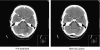

Results: Overall, PFS for the 356 UK patients was 21 weeks (95% CI: 17.6-24.7). In the 162 assessable patients, ORR was 21% (95% CI: 15-27%) and median TTP was 22 weeks (95% CI: 17-27). Efficacy was greater in capecitabine-naive patients (ORR 23 vs 16.3%, P=0.008). For 34 patients with CNS metastases, ORR was 21% (95% CI: 9-39%), with evidence of improvement in neurological symptoms, and median TTP was 22 weeks (95% CI: 15-28).

Conclusions: Lapatinib combined with capecitabine is an active treatment option for women with refractory HER2-positive MBC, including those with progressive CNS disease.